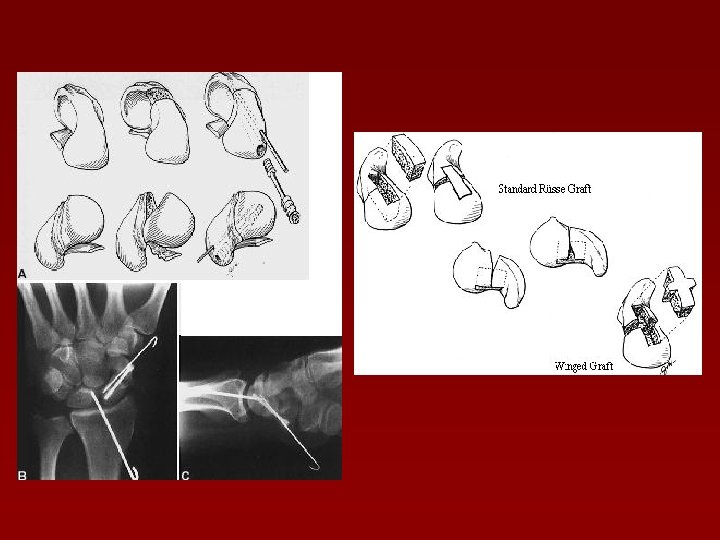

Fracturile osului lunat